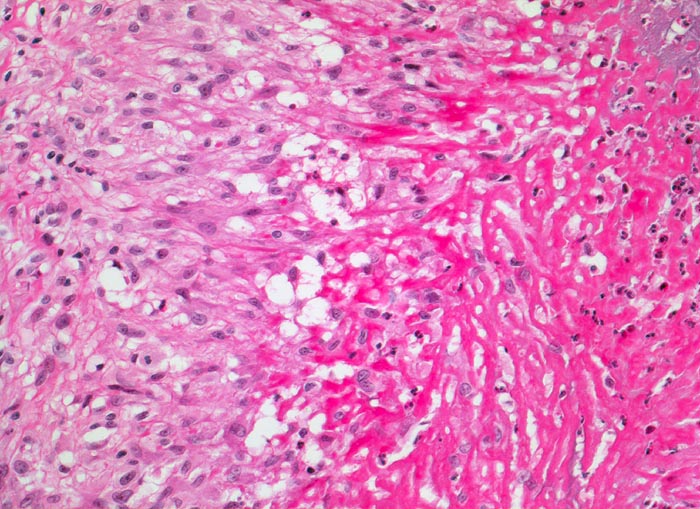

Rheumatismus nodosus

Systemerkrankung/Immunpathologie

Weichteile Arm

Rechts im Bild hypereosinophile fibrinoide Nekrose mit Einschluss von neutrophilen Granulozyten. Angrenzend an die fibrinoide Nekrose links im Bild palisadenförmig angeordnete Epitheloidzellen. Etwas weiter aussen sind locker eingestreute Lymphozyten und Granulozyten zwischen den Epitheloidzellen erkennbar.

Patientin mit rheumatoider Arthritis. Derber, verschieblicher subkutaner Knoten an der Streckseite des Unterarmes nahe des Ellenbogens.